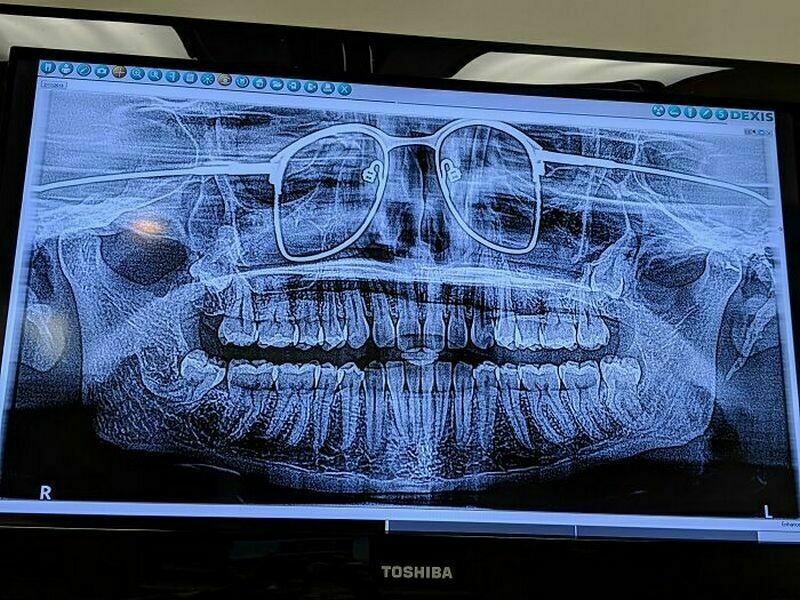

Когда сделал рентген зубов, но забыл снять очки